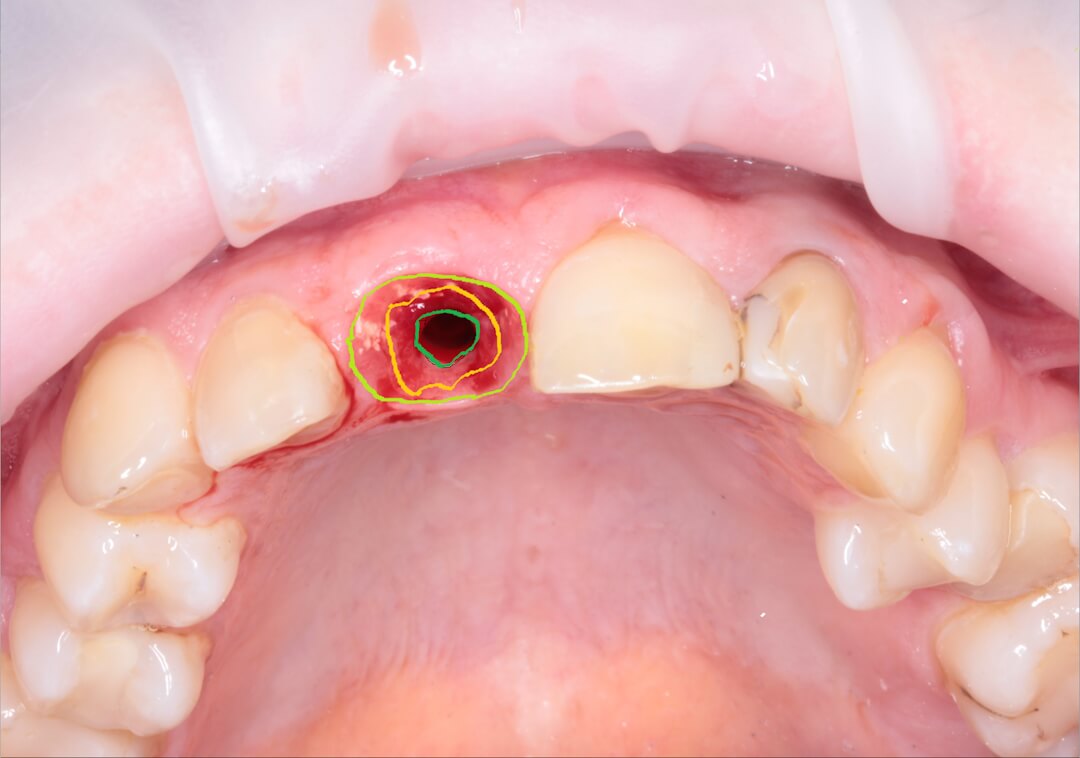

Рис. 7. На фотографии обведены Сrestal zone, Boundary zone, Esthetic zone. Зоны в профиле прорезывания коронки на дентальном имплатате, при создании которых мы можем получить максимальный эстетический эффект и максимально длительный срок службы нашей реставрации.